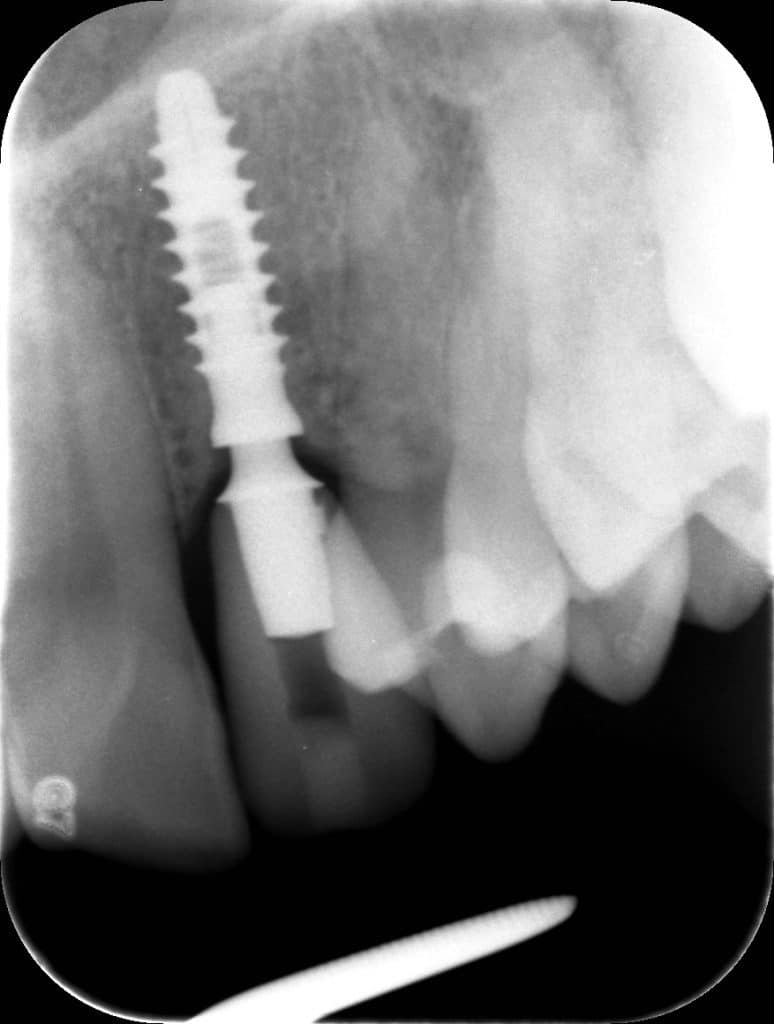

La pz N.G. di anni 52 (ASA 1) viene visitata nel mese di settembre 2017 per la mobilità ed inestetismo dell’elemento protesico 22, (foto iniziali sequenza 1) si evidenzia una frattura parziale della radice, si decide per l’estrazione ( foto sequenza 2) e sostituzione dell’elemento con un restauro implanto-protesico. Purtroppo la scarsa quota ossea apicale all’alveolo post-estrattivo (foto 2 rx) e l’alta valenza estetica dell’elemento ci rende cauti e si programma una socket preservation post estrattiva con l’ausilio delle membrane di prf (foto prf e socket sequenza 3 e 4). Durente i 5 mesi di guarigione la pz porta una protesi parziale mobile (foto 5,2) , a guarigione del sito post estrattivo si evidenzia una buona conservazione dei volumi osseo-gengivali,(foto guarigione sequenza 6) se pur presente una recessione distale all’elemnto 21.Nel mese di febbraio 2018 si procede all’inserimento di un impianto max-stability 3,75x12mm disegnando un lembo anticipato palatino per consentire un aumento dei tessuti vestibolari suturando con tecnica rool flap e trasformando l’elemento parziale mobile in una corona singola a carico immediato sul moncone temporameo applicando i concetti protesici bopt , (foto impianto moncone protesi provvisoria sequenza foto 7-8-9). Durante il periodo di maturazione dei tessuti molli vengono apportate opportune modifiche ai profili del provvisorio al fine di dare maggior spazio al tessuto gengivale, ( fotosequenza 10).Dopo circa 2 mesi dal protesizzazione provvisoria si è proceduto alla realizzazione del manufatto protesico con tecnica chair side sirona con l’ausilio del t-base (foto sequenza 11-12-13), realizzando in una sola seduta una corona in disilicato, ottenendo un risultato più che soddisfacente (Foto 14). Nel controllo a 3 mesi dal carico definitivo si apprezza la perfetta conservazione dei livelli ossei e gengivali. (foto sequenza 15).concludo con un follow up a 18 . Tengo a sottolineare che un caso come questo è stato conducibile con buoni risultati solo grazie alla piena fiducia della pz e alla sua massima motivazione e collaborazione. Ad oggi la pz sorride soddisfatta del risultato. E questo rappresenta la massima ricompensa di chi dedica tutto se stesso alla professione.